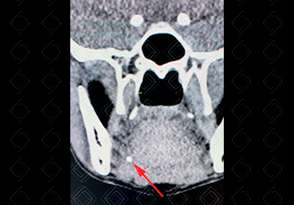

Texto alternativo para a imagem Créditos: Dra. Elazir Mota - Rio de Janeiro/RJ

Descrição da lesão: Tomografia computadorizada da face; imagem no plano coronal. Presença de cálculo na extremidade distal do ducto de Warthon direito (seta vermelha).

• Tomografia computadorizada da face : Apresenta maior acurácia para a detecção dos cálculos intraductais e intraglandulares. Idealmente, deve ser realizada após a administração do contraste venoso (irá auxiliar na caracterização da sialadenite e coleções, caso presentes);